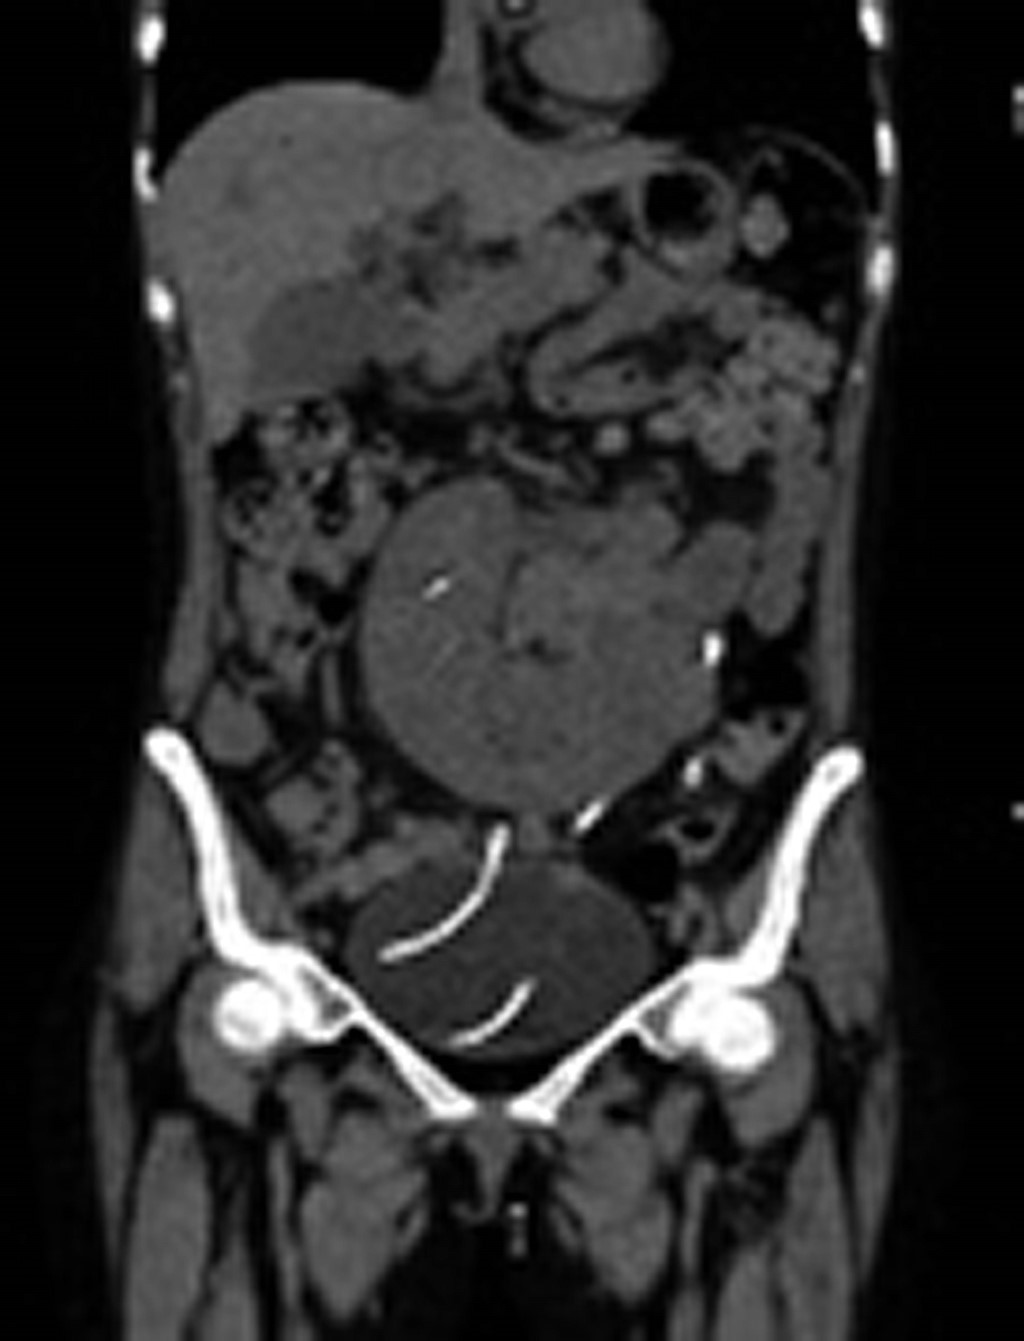

Donador masculino de 26 años, previamente sano, es declarado con muerte cerebral debido a herida por arma de fuego. Se inició protocolo de donación de órganos. Previo a la procuración, se le realizó ultrasonido renal en Unidad de Cuidados Intensivos (UCI) y los riñones no fueron reportados con anormalidades estructurales; sin embargo, al momento de la procuración se identificó riñón en herradura (Figura 1). La receptora fue una paciente femenina de 51 años, con antecedentes de enfermedad renal crónica de etiología desconocida diagnosticada en el año 2012, quién recibió un primer trasplante renal de donante fallecido en 2014, con complicaciones inmediatas de tromboembolismo pulmonar submasivo, además de rechazo mixto en 2016 con posterior disfunción crónica del injerto. Ingresó nuevamente a lista de espera en el 2019 con tasa de filtrado glomerular estimada (TFGe) CKD-EPI 13 mL/min/1.73 m2. Dados los hallazgos en la procuración y con el consentimiento de ella, recibe el injerto en herradura, el 2 de marzo de 2024. Se realizó trasplante de riñón en herradura, el cual contaba con dos arterias y dos venas por injerto, por lo que se realiza procuración en bloque con aorta y vena cava. Se realiza implante intraabdominal con abordaje por laparotomía, con anastomosis arterial terminolateral a arteria ilíaca externa derecha, y venosa terminolateral a la vena cava infrarrenal, así como doble implante ureteral independiente (Figura 2). La inmunosupresión de inducción fue con timoglobulina y metilprednisolona. Durante el evento quirúrgico se reportó sangrado de 1,800 mL, transfusión de tres unidades de concentrado eritrocitario intraoperatorio, tiempo de isquemia caliente 35 minutos, tiempo de isquemia fría cuatro horas y media. Presentó uresis espontánea tras reperfusión del injerto. En las primeras 24 horas postrasplante desarrolló estado alterado de conciencia, dificultad respiratoria, con signos de choque hipovolémico, requirió intubación orotraqueal y vasopresores. El equipo de trasplante decidió reexplorar y se descartó hemorragia, requirió soporte transfusional e ingreso en UCI. En los días siguientes evolucionó favorablemente; fue extubada, sin complicaciones, y dada de alta el 12 de marzo de 2024, con creatinina 0.4 mg/dL; actualmente, en su cuarto mes postrasplante, con creatinina de 0.6 mg/dL.

Figura 1